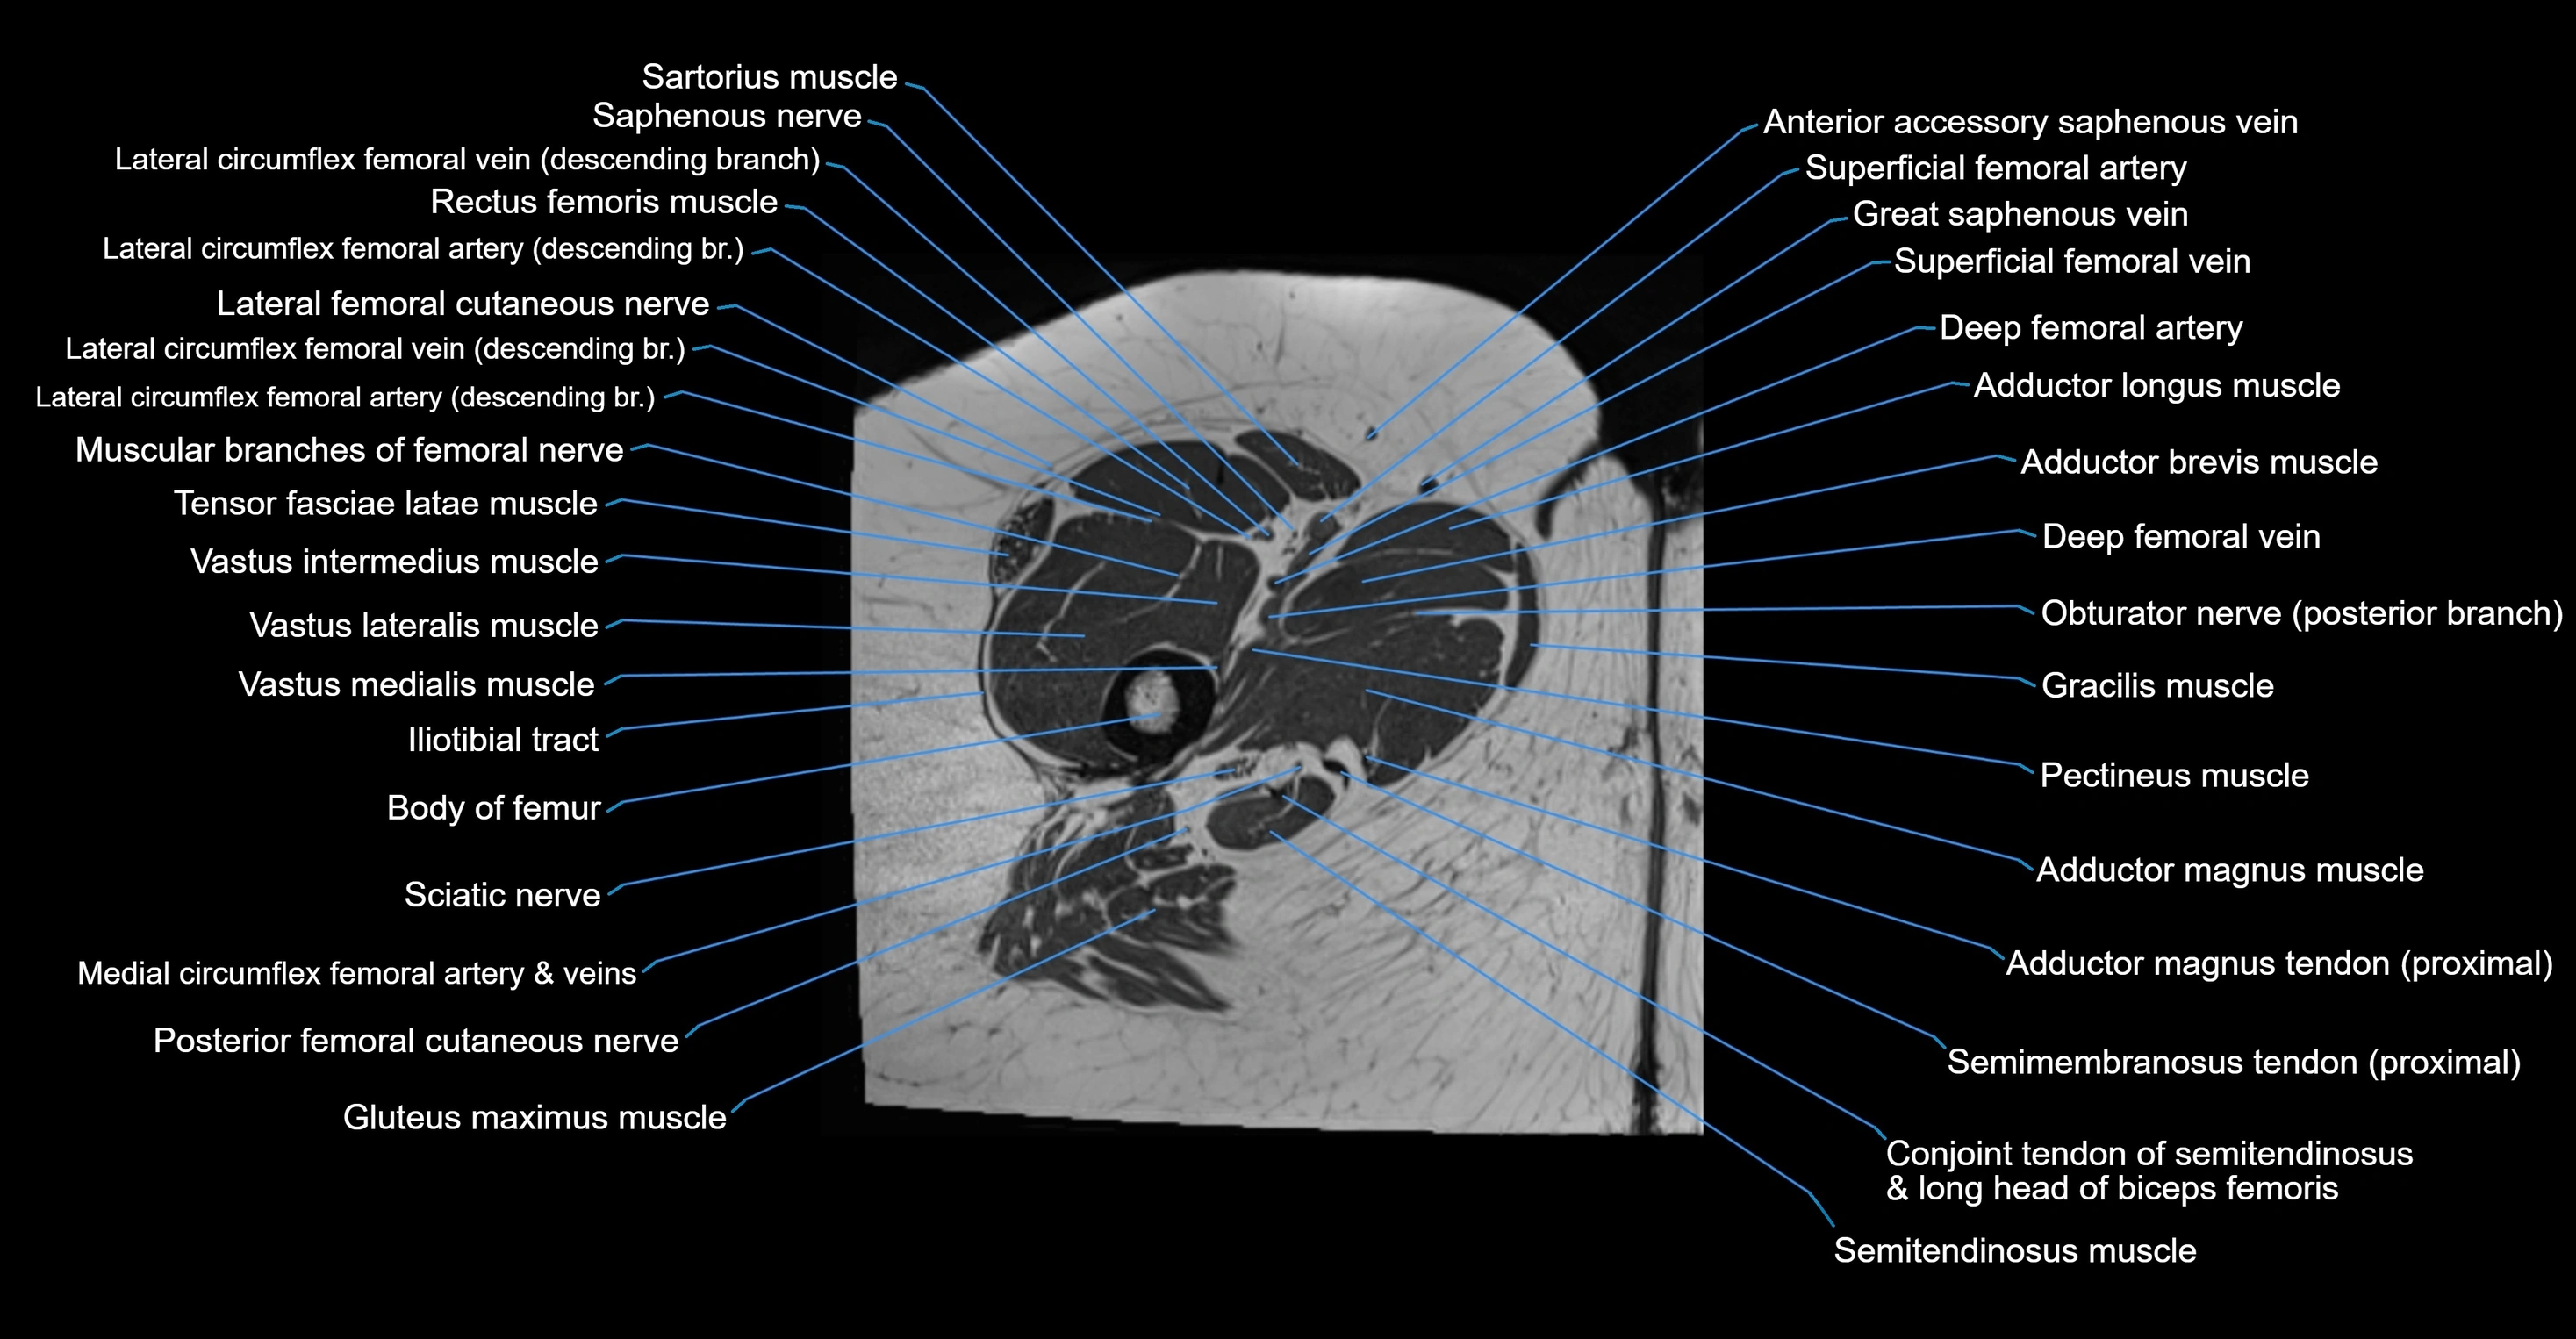

- Adductor brevis muscle

- Adductor longus muscle

- Adductor magnus muscle

- Body of femur

- Conjoint tendon of biceps femoris & semitendinosus

- Deep femoral artery (profunda femoris)

- Deep femoral vein (profunda femoris vein)

- Gluteus maximus muscle

- Gracilis muscle

- Iliotibial tract

- Lateral femoral cutaneous nerve

- Medial circumflex femoral artery

- Medial circumflex femoral vein

- Muscular branches of femoral nerve

- Pectineus muscle

- Posterior femoral cutaneous nerve

- Rectus femoris muscle

- Saphenous nerve

- Sartorius muscle

- Semimembranosus tendon (proximal)

- Tensor fasciae latae muscle

- Vastus intermedius muscle

- Vastus lateralis muscle

- Vastus medialis muscle